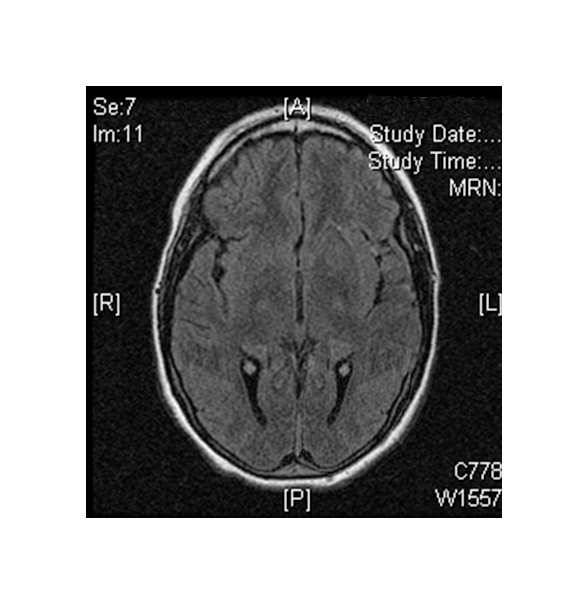

(Left) MRI scan of a healthy brain. (Right) The basal ganglia region of the brain shows abnormal signals.